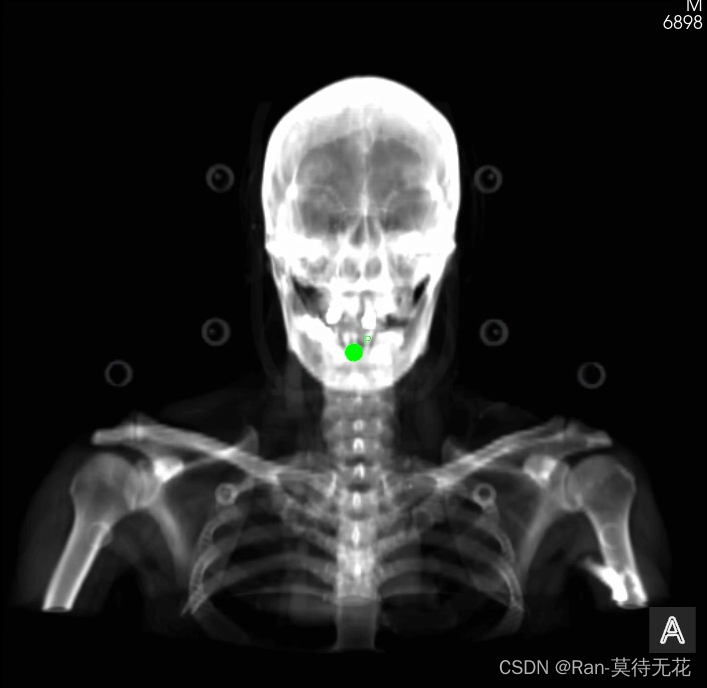

}得到的图像示例(0度):

图像中的绿点就是治疗等中心点(坐标【0,0,0】)